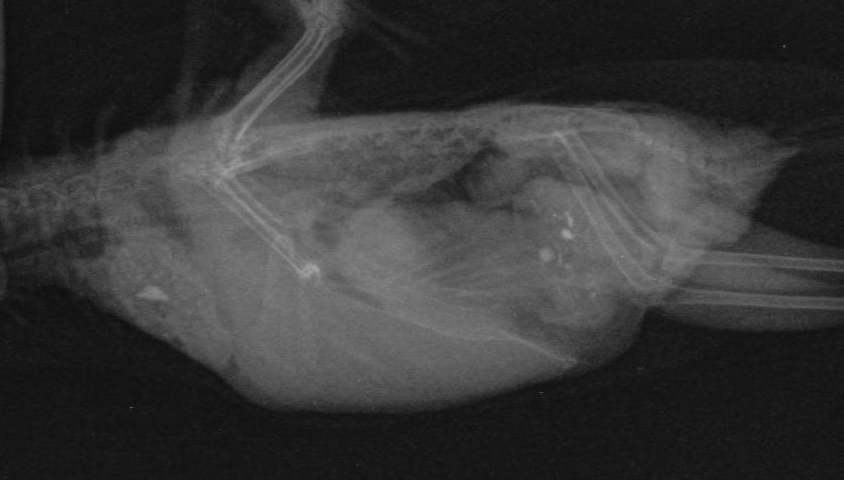

Добрый вечер! Итоги похода ко врачу Лешковой М.А.:

2. У Проши нашли опухоль семенников

3. Из-за этого повышается давление на желудок, поэтому просо плохо переваривается

4. Также из-за опухоли нарушается циркуляция крови, поэтому у Проши от сильного стресса может случиться сердечный приступ и отняться лапка

Можете опубликовать результаты рентгена и копрологии, пожалуйста?

Выходит, опухоль уже достигла значительных размеров. Бедный волнушка...